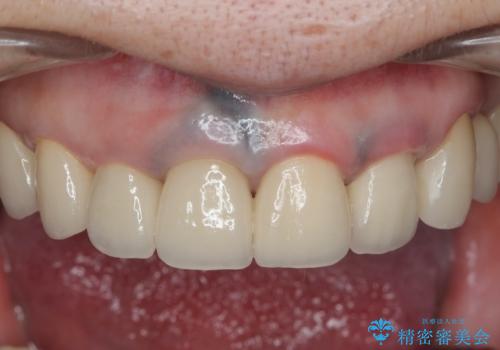

保険適応 硬質レジン前装冠から審美的でオールセラミッククラウンへ

見違えるような審美的な仕上がりに満足いただくことができました。